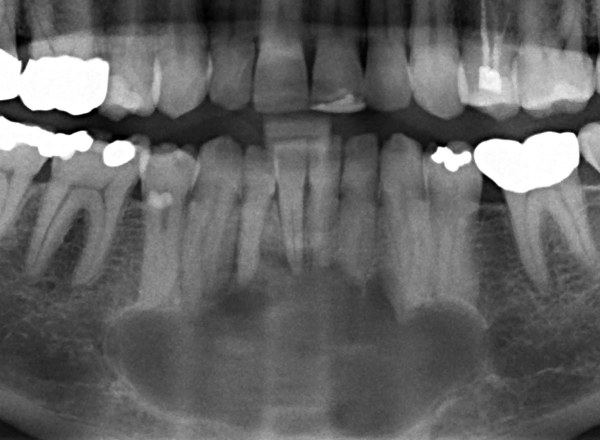

İnkşafı və böyüməsi tədricən baş verdiyindən, bu proses pasiyent tərəfindən demək olar ki hiss edilmir. Yalnız törəmənin ciddi ölçülərə çatması nəticəsində və ya iltihablanması nəticəsində meydana çıxan kliniki əlamətlər nəticəsində aşkarlanır. Əksər hallarda isə çəkilən diş və çənə rentgen şəkillərində təsadüfən rast gəlinir.